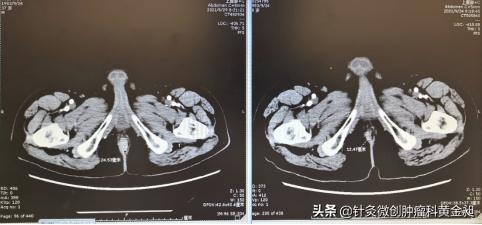

肛门区肿物2.4cm→1.2cm(左: 6月29日;右:9月24日)